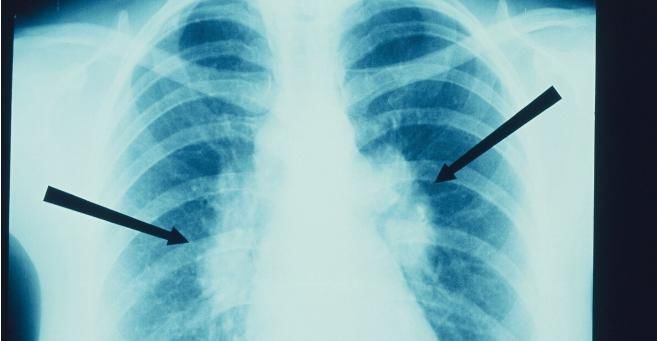

肺气肿其实是指终末细支气管远端(细支气管、肺泡管、肺泡囊、肺泡)的持久性扩大的病理状态。那么,对于肺气肿中医是如何治疗的?

肺气肿如果病情不特别严重,早期可能没有任何症状,或仅有咳嗽、咯痰,或者是仅仅在劳动过后,或者是在运动过后会感觉到气短。根据肺气肿的表现,它属于中医范畴的\\'\\'咳喘\\'\\'、\\'\\'肺胀\\'\\'、\\'\\'气短\\'\\'等。